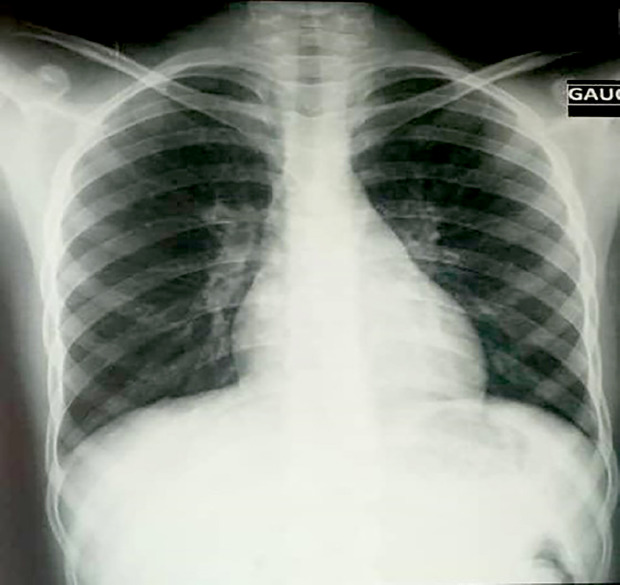

Case description: The patient presented with fever (39.3°C), general deterioration, Glasgow Coma Scale score of 10/15 without motor deficits, neck stiffness, and helmet-like headache unresponsive to analgesics. The patient had a CD4 count of 932 cells/mm3. No other immunosuppressive conditions were noted. The diagnosis of NMC was confirmed based on clinical and microbiologic findings. The patient was successfully treated in Bamako using an alternative protocol with fluconazole, a more accessible, less expensive treatment with fewer side effects compared to amphotericin B.

Abstract Image